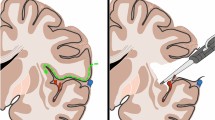

The transsylvian transinsular approach

After a fronto-temporal craniotomy, the dura is opened above the sylvian fissure and retraction is applied to the lateral fronto-orbital area to demonstrate the carotid cistern. The latter is opened between the optic nerve and internal carotid artery. The proximal part of the sylvian fissure is then opened, exposing approximately the anterior one-third of the insula and 1–2 cm of the M2 segments. By opening the sylvian fissure, the temporal operculum can be retracted downward to expose the inferior part of the insula down to the inferior limiting sulcus (Fig. 4a). The anterior tip of the temporal horn is located approximately 3 cm posterior to the temporal pole. The M2 branches have been retracted (dashed black line) along the inferior limiting sulcus. The anterior half of the inferior limiting sulcus was found to be devoid of larger perforating arteries. An incision lateral to the inferior trunk between the M2 branches (Fig. 4b); approximately 1.5–2 cm in length in the inferior limiting sulcus of the insula provides access to the temporal horn. The approach exposes the hippocampus and the collateral eminence in the floor of the temporal horn.

Photographs show the right the transsylvian transinsular transchoroidal approach to the basal cisterns. a The sylvian fissure is opened and the temporal operculum is retracted to expose the anterior half of the insula and the M2 branches; b specimen shows the cortical incision (dashed black line) through the anterior portion of the inferior limiting sulcus parallel to M2 branches; c the temporal horn and choroidal fissure (arrow) are exposed; d the choroidal fissure is opened on the forniceal side by separating the choroid plexus from the fimbria of the fornix to expose the ambient cistern. e Removal of the portion anterior temporal lobe, the choroids plexus has been elevated toward the thalamus to expose the ambient cistern, and expose the lateral geniculate body, basal vein, and P2 segment of the PCA. f Coronal section. Arrow demonstrates the transsylvian trans-insular transchoroidal approach to the ambient cisterns

After the temporal horn is entered, the hippocampus and the choroid plexus can be observed. The choroidal artery and numerous venous branches pass through the tenia thalami; opening the choroidal fissure (Fig. 4c) between the fimbria and choroid plexus avoids damage to these vessels. Elevating the choroid plexus toward the thalamus can expose the upper portion of the posterior crural cistern and the ambient cistern; the basal vein is the first structure encountered (Fig. 4d). The upper part of the ambient cistern medial to the choroidal fissure is located on the superior surface of the parahippocampal gyrus. The dentate gyrus and parahippocampal gyrus are located medial and caudal to the choroidal fissure and are part of lateral wall of the ambient cistern. The optic tract is visible anteriorly, and the lateral geniculate body and thalamus are visible posteriorly (Fig. 4e). These structures are medial and rostral to the tenia fimbriae and thus difficult to injure if dissection proceeds carefully. The shortest distance between inferior limiting sulcus and the roof of the temporal horn is 6.5 ± 1.78 mm; the mean distance from limen insulae to the lateral geniculate body is 33.0 ± 2.94 mm.